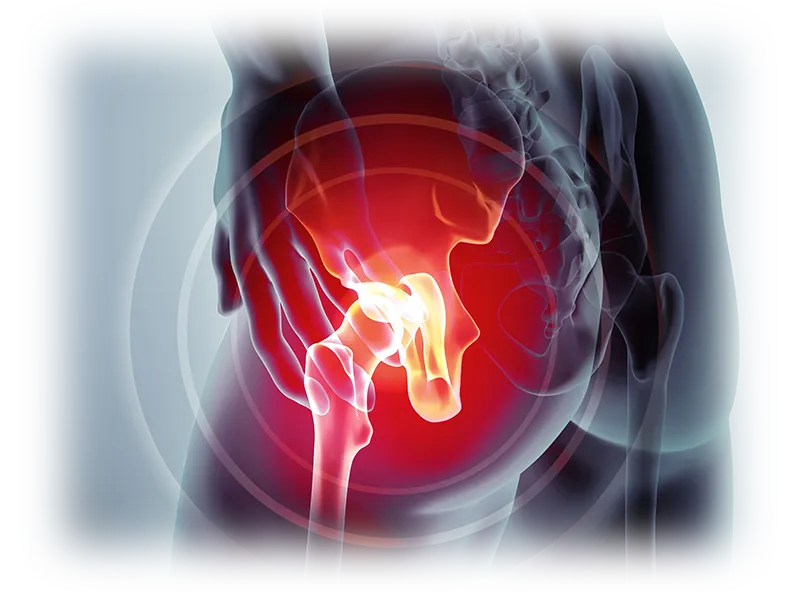

고관절 통증 원인 3. 고관절 관절염

고관절 관절염은 고관절에 염증성 병변이 있는 상태로, 이는 관절염이 고관절까지 영향을 미쳤다는 뜻입니다. 고관절 관절염의 원인은 매우 다양합니다. 가장 대표적인 예로는 퇴행성 고관절 관절염이 있는데, 이는 과도한 사용과 노화로 인해 고관절이 퇴행하고 대퇴골 연골이 점차 닳아 없어지는 질환입니다.

관절염에는 골관절염과 류마티스 관절염 같은 다양한 종류가 존재합니다. 관절염에 걸리면 염증이 있는 관절 주변에서 통증이 발생해 이동성이 감소하며, 걷거나 일상적인 활동을 하는 데 어려움을 겪을 수 있습니다.

걷거나 달릴 때 고관절 부위의 통증이 더 심해질 수 있고, 다리를 완전히 펴는 것조차 어려워질 수 있습니다. 패혈증성 관절염은 심한 관절 통증과 함께 발열을 동반합니다.